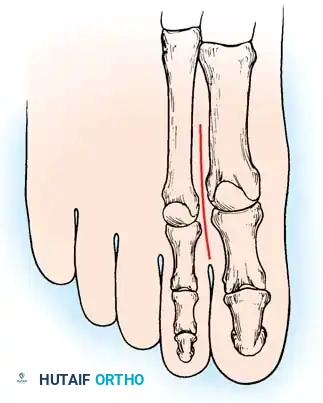

2. Jones Procedure (EHL to First Metatarsal Neck)

* Rationale: Corrects flexible clawing of the hallux and elevates the first ray.

* Technique: Transect the EHL at the IP joint. Reroute it through a drill hole in the neck of the first metatarsal and suture it back onto itself. The IP joint of the hallux must be arthrodesed to prevent a secondary drop-toe deformity.